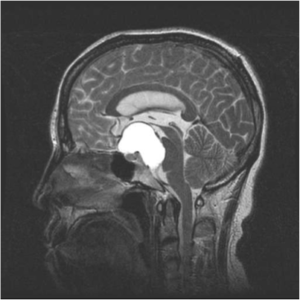

MRT-Bilder eines Kraniopharyngeom mit Druck auf die Sehnervenkreuzung (Chiasma).

Intraoperative Bilder einer Operation eines Kraniopharyngeom vor und nach Tumorentfernung mit freier Sehnervenkreuzung (Chiasma).